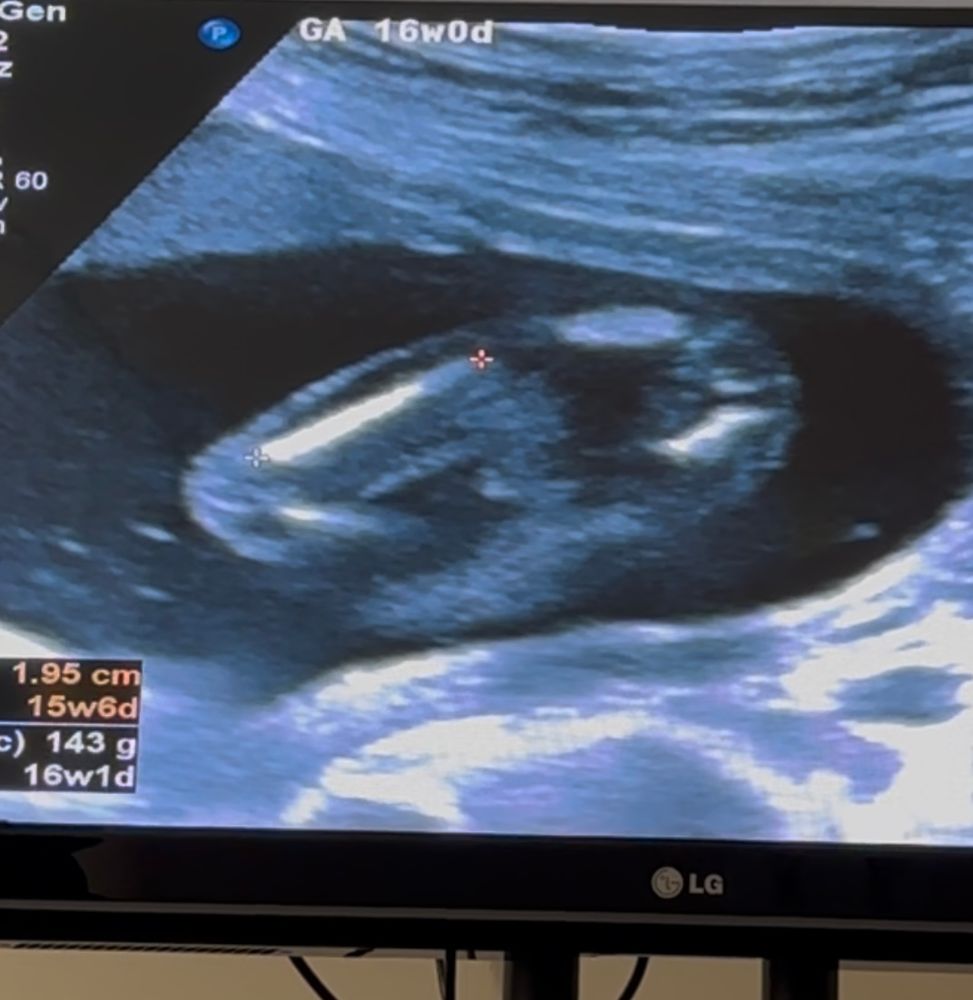

Врач сегодня увидела на 100% по ее словам, завтра будем резать торт узнавать) а я во время узи успела увидеть мальчика на этом моменте) как думаете может от еще оказаться девочкой?

Не совсем чётко видно, поэтому сложно сказать. У дочи половые губки прям видно было, как разделены между собой и похожи были на кофейное зернышко.

По вашему снимку я больше к мальчику склоняюсь

На этом фото не особо понятно, но вроде губы 🤨

sunny , когда узист смотрела пол попросила закрыть глаза, думаю было точно видно потому что она сказала что уверена на 10000% 😃 а это стоп кадр из видео что я снимала когда измеряли бедро